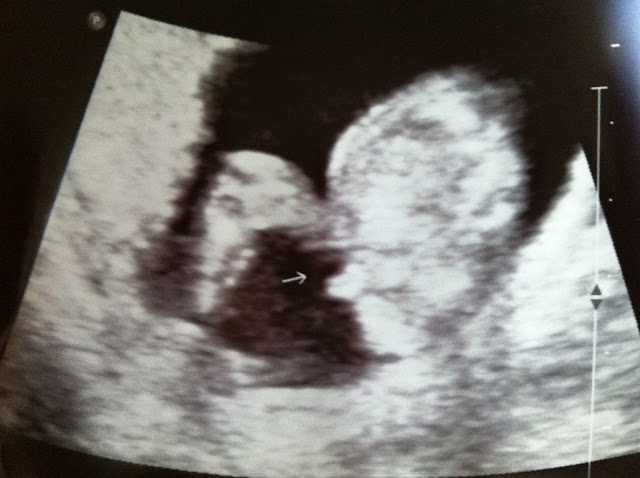

Then the next day we had our doctors appt. and I thought I might have to fight them a little bit to see if we could find out what it is but she walked in, we talked a little about eating and my weight (I lost 3 lbs :[) and then she said "should we do an ultrasound and find out what it is." YAY! I was so happy. I love my OBGYN (and not just because she let me find out what it was.)

Jarom wanted a girl but felt like it was a boy. I wanted either one but felt like it was a girl. It is...

Pretty obvious. :] She hadn't said anything yet and I said "it looks like a boy to me." When I found out it was a boy all I could think of was "how am I suppose to raise a boy?" I guess I didn't realize how much I really thought it would be a girl (I guess I got a little attached to frilly cute clothes and headband flowers) but I know that we are suppose to have this spirit come to our family and he will be such a blessing to us!

Waving to us. :] He was so bouncy. I didn't know if he would stop moving for us to get a good view. He seems very energetic. Except I have no idea how I am not feeling him. When I was looking at the screen all I could think was "is this a fake video that they turn on every time they check me" He was everywhere and I felt nothing.

Then right at the end, after he had given us a show he kicked back and relaxed. I love this picture. That's his little leg on the right and he is just chillin. :]